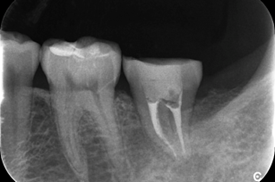

Er:YAGレーザーを併用した歯周組織再生療法の症例紹介

Before

初診時歯周ポケット6mm、左上4番に骨吸収を認める

切開はEPPT(entire papilla preservation technique)

治療中

エムドゲイン®サイトランス®を填入し、レーザーにて血餅形成、縫合

After

骨の再生を認める

主訴

他院で歯周病と言われ紹介されました

治療内容

歯周基本治療後に再評価し、ポケットが残存したのでEr:YAGレーザーを併用した歯周組織再生療法(エムドゲイン® 、サイトランス®を使用)を行ったケース

治療費

16万円(税込)

治療期間

6ヶ月

治療回数

8回

想定されたリスク

※術後の知覚過敏や歯肉退縮の可能性がありました。

歯周病の好発部位である上顎第一小臼歯近心面における骨吸収に対して再生療法を行ったケース。一般的に根面溝という溝があり歯石の沈着が生じやすい。また溝の存在により術後に歯肉と歯根の付着が生じにくいため、今回はEr:YAGレーザーにて血餅形成を行い組織の安定化を図った。